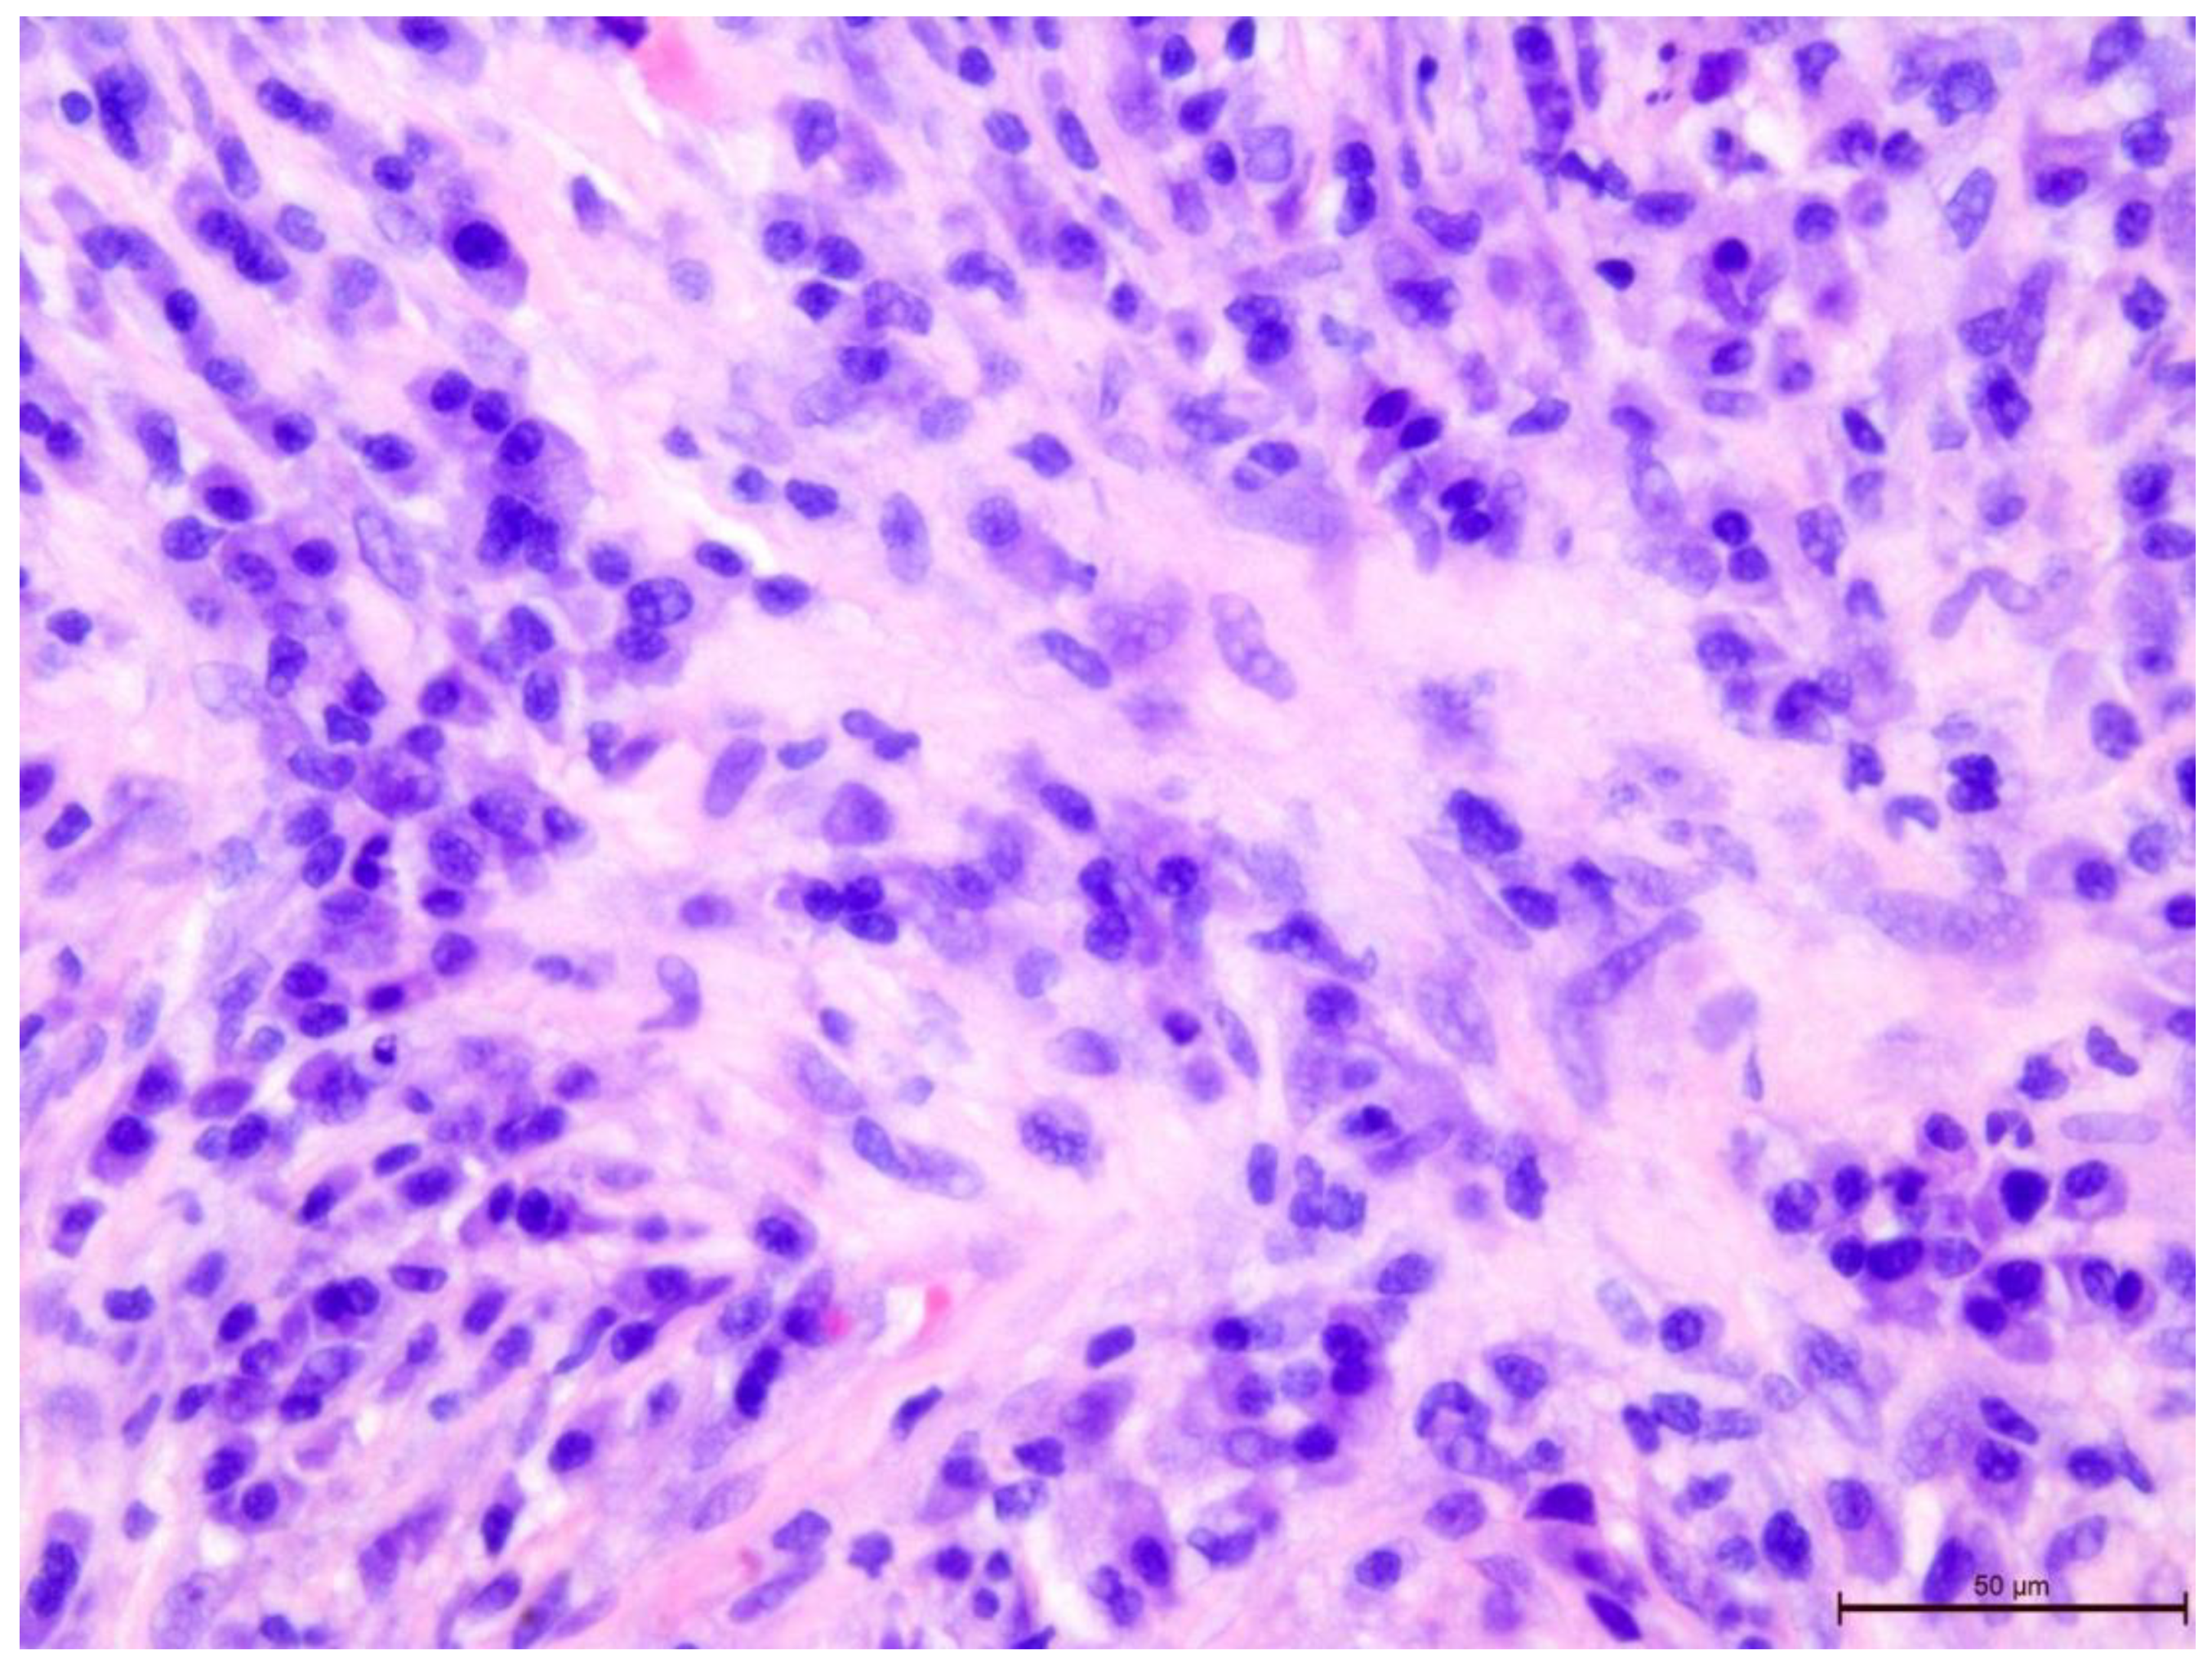

The T-lymphocyte infiltration in the tumor stroma was assessed according to the recommendations of the International Working Group on Immuno-Oncology of Breast Cancer Biomarkers (Figure 2, Figure 3, Figure 4, Figure 5, Figure 6 and Figure 7). The results are reported as the percentage of lymphocytes in the tumor stroma.

Figure 6. Invasive breast cancer with 20% T-lymphocyte infiltration in the tumor stroma, H&E staining, area 400×.

Preprints 109573 g006

Figure 7. Invasive breast cancer with 90% T-lymphocyte infiltration in the tumor stroma, H&E staining, area 400×.

Preprints 109573 g007